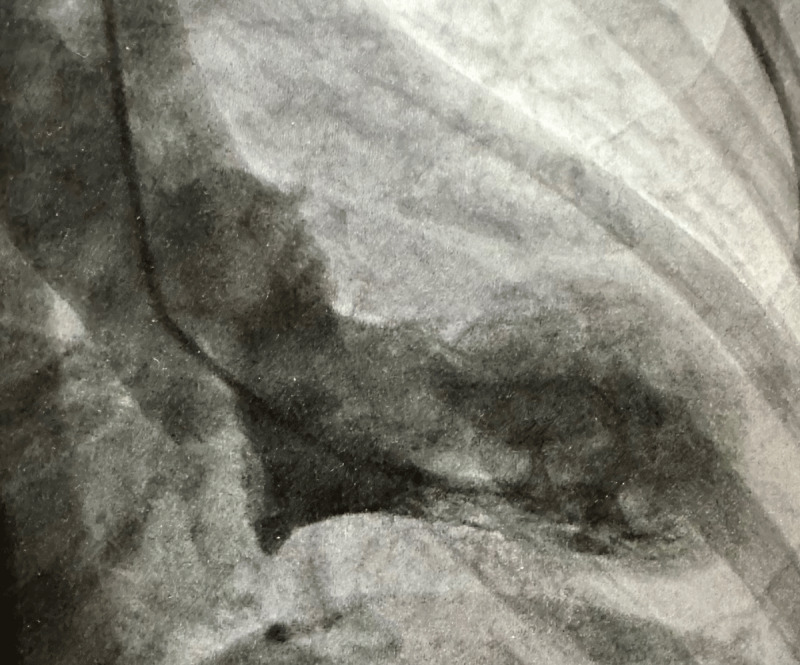

This Points to Remember column discusses the differential diagnosis of acute myocardial infarction with normal coronary arteries, one example of which is Takotsubo cardiomyopathy. In the case presented below, the diagnosis of Takotsubo cardiomyopathy was based on the characteristic appearance of the left ventricular apical bulging, normal coronary arteries, and the resolution of the wall motion abnormalities within a relatively short period of time.

本期 "要点记忆 "专栏讨论冠状动脉正常的急性心肌梗死的鉴别诊断,其中一个例子就是 Takotsubo 心肌病。在下面介绍的病例中,Takotsubo 心肌病的诊断依据是左心室心尖隆起的特征性外观、正常的冠状动脉以及在相对较短的时间内室壁运动异常的缓解。